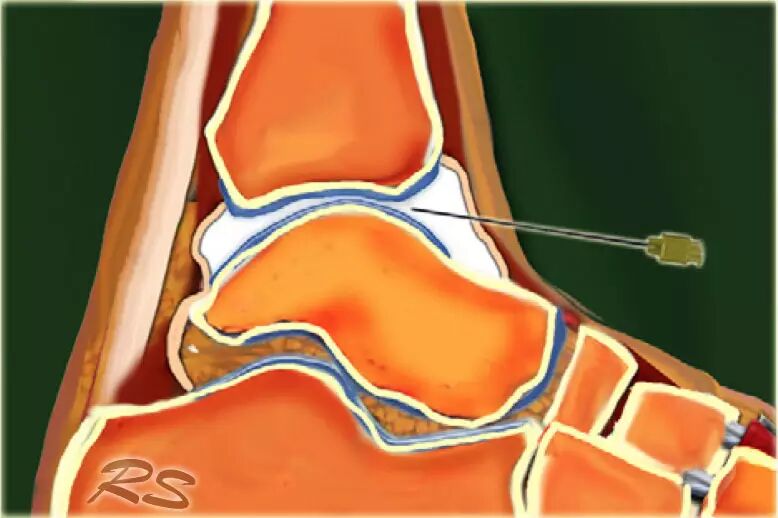

胫骨关节      CT或MR关节镜可用于查询韧带,骨软骨或软骨损伤,评价自由体或查询骨软骨病变的稳定性。对于踝关节(胫骨关节)的注射,患者仰卧,足部轻微的跖屈。用超声波检查胫骨关节的内侧,以确定合适的注射部位,同时检查任何过量的关节液。我们使用小型弯曲阵列8 MHz传感器,但如果优选,可以使用18-12 MHz线性阵列传感器。 探头的长轴保持在矢状面内。

通常为22号(长度:30mm)的针被引入与在前关节空间的内侧上的换能器的长成像轴线,内侧到前胫骨韧带,避免韧带和血管。应该确定距骨穹顶和悬垂的前胫骨唇。 针头在胫骨远端成角度地进入远侧胫骨的腹侧唇下的关节,瞄准远侧胫骨的关节表面。感觉到接触,并且再次确保针尖离开胫骨软骨并且斜面面向接头。

将8-10ml的对比剂注入胫骨关节,并且看到前囊与流体一起膨胀。

患者不应该有疼痛而抵抗。